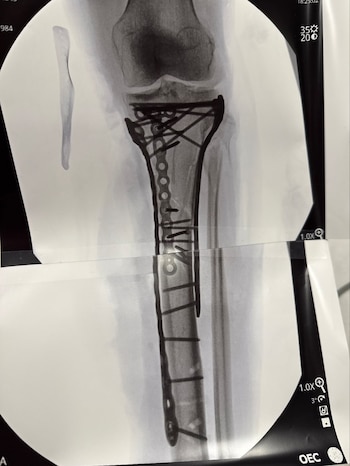

La recuperación de Lindsey Vonn tras el impacto sufrido en los Juegos Olímpicos de Invierno de Milano-Cortina reveló imágenes que parecen irreales: una radiografía de su pierna izquierda con varios tornillos metálicos y placas que ahora forman parte de su anatomía. La propia Vonn se refirió a su condición con ironía: “Soy biónica de verdad ahora”, expresó y subrayó el impacto físico y mental de esta etapa.

Ya en su perfil de Instagram, profundizó en sus sensaciones y lo acompañó de un video de ella en la camilla y una imagen de la radiografía en cuestión: “Como pueden ver han sido necesarias muchas placas y tornillos para recomponerlo todo. Debido a la gravedad del traumatismo, he tenido algunas dificultades después de la operación y aún no me han dado el alta del hospital... pero ya casi estoy lista. Pasito a pasito. Pronto explicaré la lesión y lo que significa todo esto”.

La mujer de 41 años fue sometida a cinco cirugías en menos de dos semanas, cuatro de ellas en Italia y una más en Estados Unidos tras lograr el alta médica y regresar a su país. La complejidad de la fractura en la tibia izquierda, combinada con el antecedente de múltiples lesiones previas y la existencia de implantes de titanio en su rodilla derecha, pone de relieve la magnitud de la situación. En palabras de la propia deportista: “Mi lesión fue mucho más severa que una simple fractura de pierna. Sigo asimilando lo que significa y el camino que tengo por delante”, escribió en redes sociales.

El doctor Bertrand Sonnery-Cottet, referente en ortopedia y cirugía de rodilla, advirtió en una entrevista con RMC Sports sobre el riesgo real que afrontan pacientes con lesiones tan graves: “Algunas lesiones como la suya pueden acabar en amputación”, aunque aclaró que el caso de Vonn no llegó a ese punto. El procedimiento más reciente, que duró más de seis horas, implicó la utilización de numerosas placas y tornillos para estabilizar la fractura. La atleta agradeció al equipo médico y relató que el dolor fue intenso, lo que dificulta su recuperación inmediata.